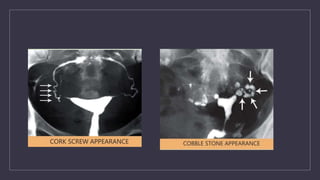

Comment on this picture

How to manage..?

HSG findings in Genital TB

FALLOPIAN TUBES

Specific findings

• Beaded tube

• Golf club appearance

• Pipestem app

• Floral app

• Leopard skin app

Non specific findings

• Hydrosalphinx

• Mucosal thickening

• Peritubal adhesions(tobacco pouch app, loculated spill, cockscrew app